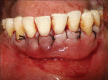

Gingival recession is defined as the apical migration of the gingival margin with exposure of root surfaces. The etiology of the condition is multifactorial. Given the high rate of gingival recession defects among the general population, it is imperative that dental practitioners have an understanding of the etiology, complications and management of the condition. A recent innovation in dentistry is the preparation and use of platelet-rich fibrin (PRF) for recession defects. The article presents a case report, which highlights the use of lateral sliding bridge flap along with PRF in a collagen membrane carrier (guided tissue regeneration) for the treatment of multiple recession defects.